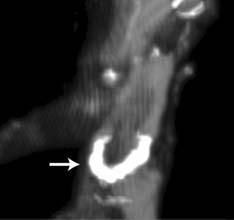

An international group of researchers used computed tomography (CT) scans in the Horus Study to look for the characteristic signs of atherosclerosis — vascular calcification, or build-up of a hard calcified substance along the walls of arteries — in 137 mummies from ancient Egypt, Peru, southwest America and the Aleutian Islands in Alaska. This was one of the most popular clinical studies presented during the American College of Cardiology (ACC) 2013 meeting.

Where the mummies' arterial structure had survived, the researchers were able to attribute a definite case of atherosclerosis where they found signs of vascular calcification. In some cases, the arterial structure had not survived mummification, but the calcified plaque was still present in sites where arteries would have once been, in which case the researchers attributed a probable case of atherosclerosis.